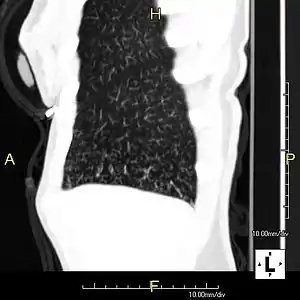

مقطع سهمي لصورة بالأشعة المقطعية يظهر علامة "شجرة في برعم" لمسالك هوائية صغيرة قاصية متأثرة بمتلازمة كارتاجنر.

في علم الأشعة، فإن علامة شجرة في برعم التي يمكن مشاهدتها في التصوير المقطعي المحوسب تدل على درجة ما من انسداد المسالك الهوائية.[1]

علامة شجرة في برعم تدل على وجود عدوى منتشرة داخل القصيبات وترتبط بالإصابة بالسل وذات الرئة القصبي.